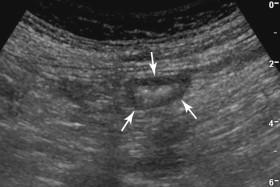

F igure 9-2, Normal colon. Transverse view of the colon shows the typical bull's-eye appearance of collapsed bowel (arrows) .